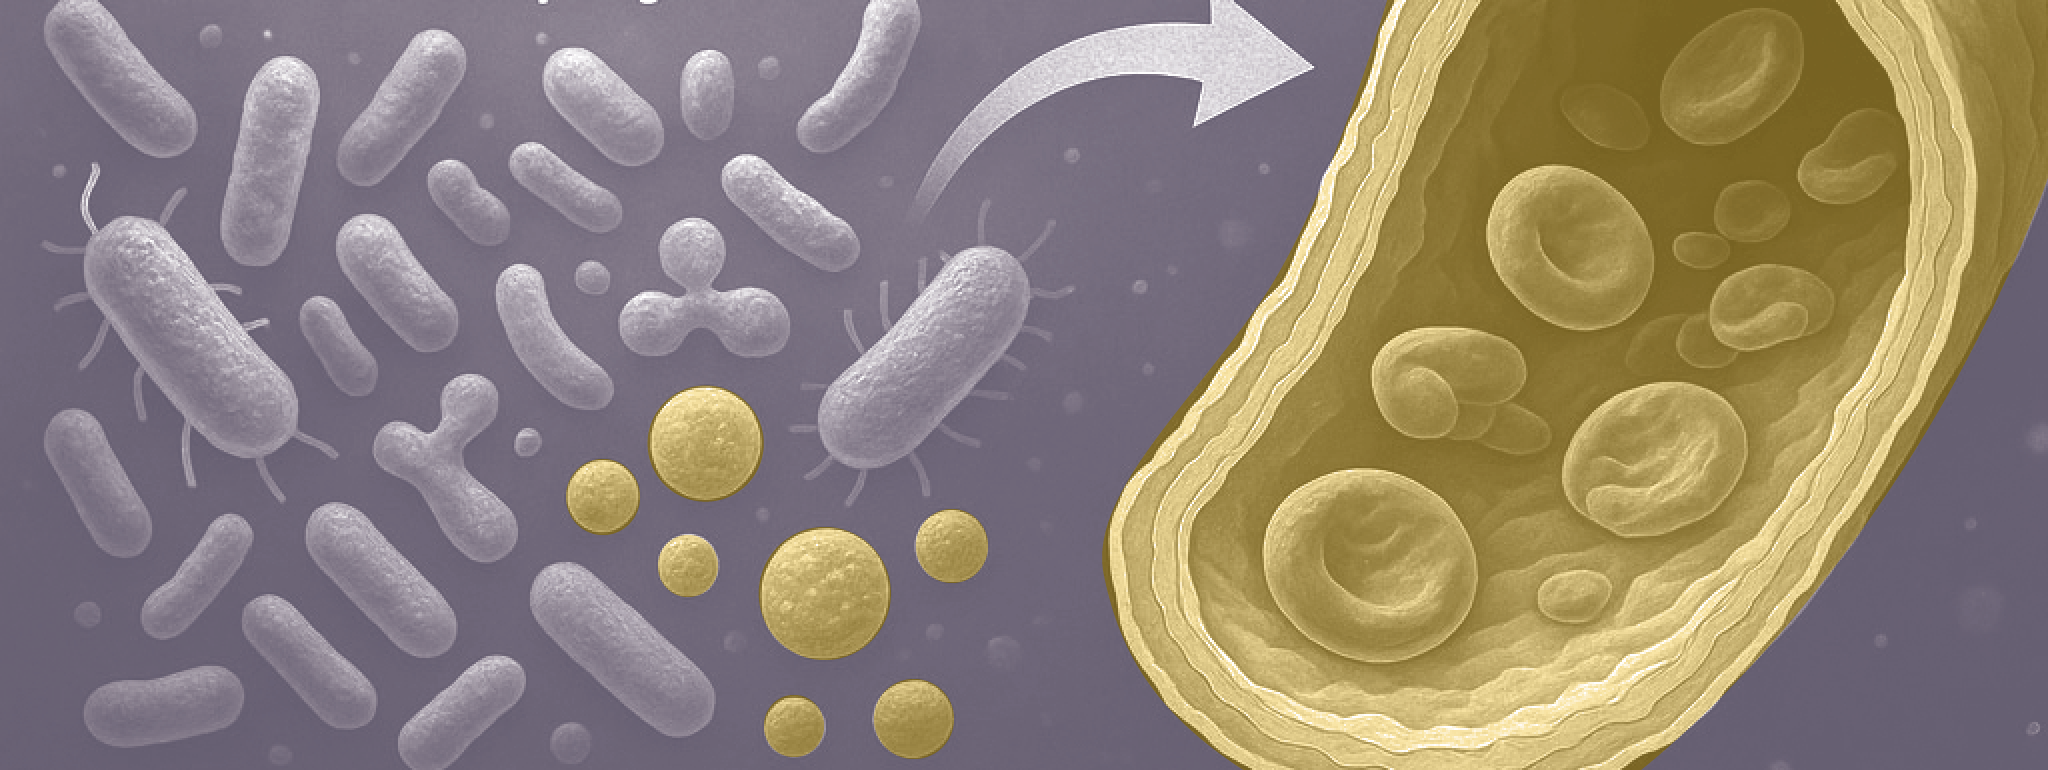

Onderzoekers van de Universiteit van Zürich laten zien dat darmbacteriën en hun metabolieten direct bijdragen aan de veroudering van bloedvaten. Met name fenylazijnzuur, een afbraakproduct van het aminozuur fenylalanine, speelt een sleutelrol in dit proces.